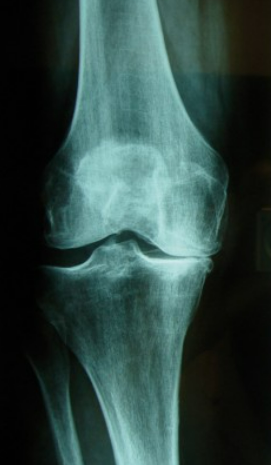

L'arthrose du genou se voit sur des radiographies

Des radiographies de genou permettront de poser le diagnostic

Selon vos examens radiographiques et l'importance de votre arthrose deux types de prothèse existent